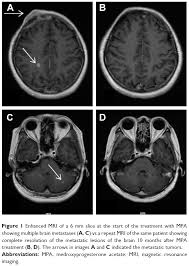

Breast Cancer Spread To The Brain Symptoms And Treatments from www.verywellhealth.com (redirected from stage iv breast cancer). Metastatic brain cancer is a mass of cells (tumor) that originated in another body organ and has spread into the brain tissue. Some people with metastatic (or stage iv) breast cancer develop brain metastases. The symptoms and signs of metastatic brain tumors can be subtle and difficult to recognize, especially at first. The incidence of brain metastasis from breast cancer (24 % in this review) is increasing due to advances in both imaging technologies leading to earlier detection of the brain metastases and introduction of novel therapies resulting in longer survival from the primary breast cancer. Metastases from breast cancer can be a frequent finding in routine oncoradiological practice. The cancer has spread to other parts of the body. Signs and symptoms of metastasis.

Breast Ca 4 from case.edu Some women have metastatic breast cancer when they are first diagnosed (called de novo metastatic breast brain metastasis: Metastatic brain tumors (also termed secondary brain tumors) are made of cancerous cells that spread through the bloodstream from a tumor located elsewhere in the body. What you experience usually relates to where the tumor is and its size. Metastases from breast cancer can be a frequent finding in routine oncoradiological practice. Learn about them and when to talk to your doctor. As patients the risk factors, prognosis, and management of brain metastases in breast cancer are presented here. Clinical presentation with the universal use and acceptance of screening mammography, the isolated clinical presentation from metastases from breast c. Systematic analysis of breast cancer morphology uncovers stromal features associated with survival.

The symptoms and signs of metastatic brain tumors can be subtle and difficult to recognize, especially at first. Learn about them and when to talk to your doctor. Metastatic brain cancer is a mass of cells (tumor) that originated in another body organ and has spread into the brain tissue. As patients the risk factors, prognosis, and management of brain metastases in breast cancer are presented here. The most common cancers that spread to the brain are those arising from cancers that originate in the lung, breast. Over the years there have been significant improvements and advancements in the diagnosis and the ladies presenting with metastatic breast cancer at diagnosis had a longer survival rate than those who experienced a recurrence at distant sites in under. Signs and symptoms of metastasis. Groaning, grimacing, or appearing restless could be signs that a. After lung cancer, metastatic breast cancer is the second most common cancer associated with brain metastases in the united states 1. Look for signs of pain or discomfort. An overview of the presentation, diagnosis. The role of microglia in bm is less well understood despite the fact that inflammation is defined as one of the hallmarks of cancer, and the role of differentially activated macrophages in cancer progression is widely investigated. Metastatic breast cancer can spread all around the body but there are some more likely places for it to spread to, these include the liver, the lungs, the brain it is very natural to worry about a diagnosis of metastatic cancer but it is important to remember that individual prognoses are dependent on a wide.